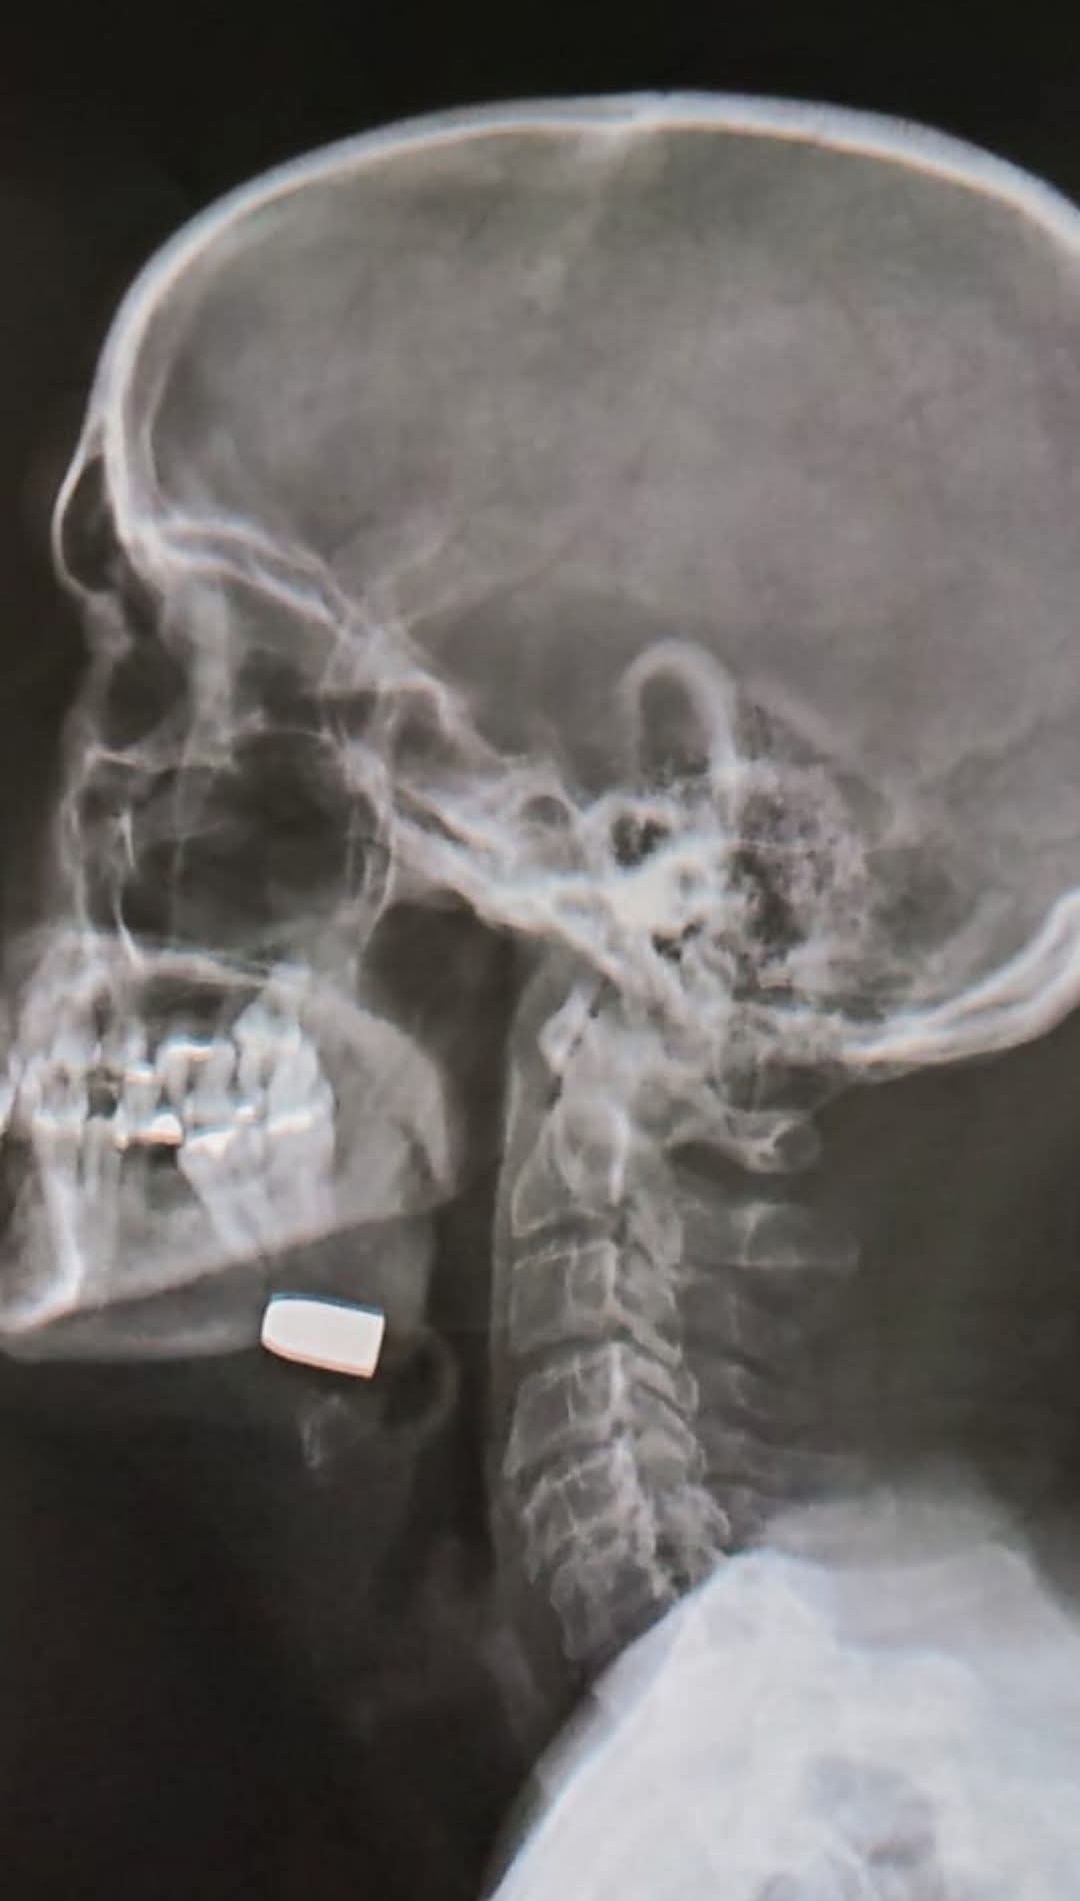

O pastor Jorge Antônio Rodrigues foi atingido no rosto por uma bala perdida enquanto dormia em sua residência passou por cirurgia e está fora de perigo. O religioso, que foi baleado na madrugada da última sexta-feira, se recuperava de uma cirurgia de hérnia.

Segundo relato da filha da vítima, Hilem Rodrigues, o pastor foi levado inicialmente à UPA, onde recebeu pontos no ferimento e acabou liberado. No entanto, ao longo do dia, as dores aumentaram e, em nova avaliação, os médicos constataram que o projétil permanecia alojado. Diante da situação, ele foi transferido para o Hospital Elmíria Silvério Barbosa, onde passou por cirurgia para a retirada da bala.